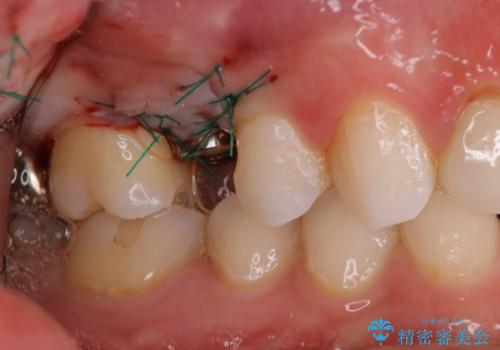

- 数年前に他医院で抜歯したままで過ごし、今回歯を入れたいとのことで来院された患者様です。

治療回数を短くしたいと1DAYインプラントを希望されました。

インプラント埋入手術は1回で全て行い、2ヶ月後にはセラミック治療で、審美回復と機能回復をしました。